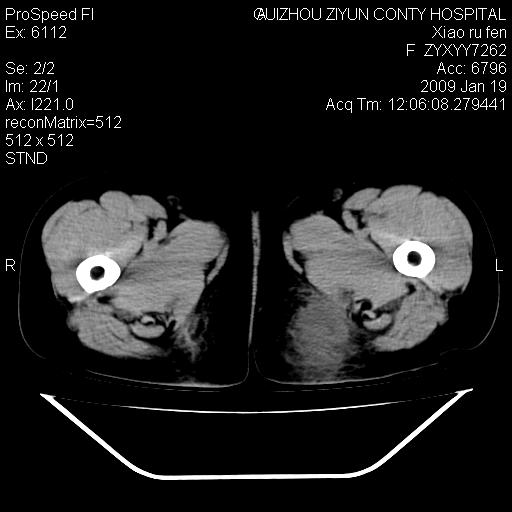

以下是引用随光逐影在2009-1-19 16:15:00的发言:[br]左侧臀部类似软组织密度肿块,性质待定(不排除肿瘤可能);建议行进一步检查。

以下是引用zbp537在2009-1-19 14:25:00的发言:[br]考虑两个诊断:1、皮脂腺囊肿伴感染。2、脓肿。[br]诊断依据:[br]1、肿块为低密度,边界较清,和皮肤相连,周围结构清晰,未见受累及。[br]2、诊断脓肿是因为其内密度不均匀,当然要结合病史,因为脓肿临床上肯定表现为红肿热痛,也希望楼主把病史提供全面些,这些便于讨论。

以下是引用zbp537在2009-1-19 14:25:00的发言:[br]考虑两个诊断:1、皮脂腺囊肿。2、脓肿。[br]诊断依据:[br]1、肿块为低密度,边界较清,和皮肤相连,周围结构清晰,未见受累及。[br]2、诊断脓肿是因为其内密度不均匀,当然要结合病史,因为脓肿临床上肯定表现为红肿热痛,也希望楼主把病史提供全面些,这些便于讨论。